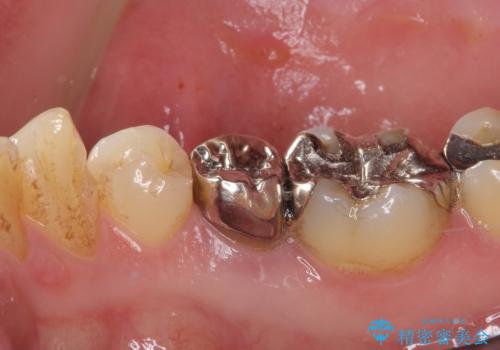

残念ながら抜歯が必要となりましたが、しっかりと診断を行ったことで、患者様も抜歯に納得していただけました。

抜歯後は痛みがあっという間に引き、ブリッジ補綴後は安定して咬めるようになりました。